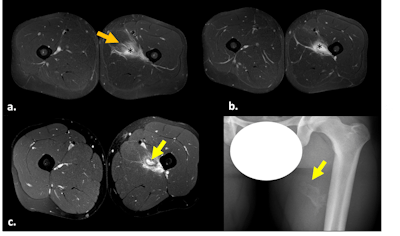

Ultrasound longitudinal view of distal biceps brachii tendon tear (a). A month later, MRI fat-suppressed proton-density sagittal (b), axial (c), and forearm supinated (FABS) position (d) sequences were performed. Complete full-thickness tear of the distal tendon of the short head of the biceps brachii is visible, with retracted and thickened torn end at the MTJ (white arrow). Some isolated fibers of the partially torn long-head tendon are visible in the radial tuberosity (orange arrow).